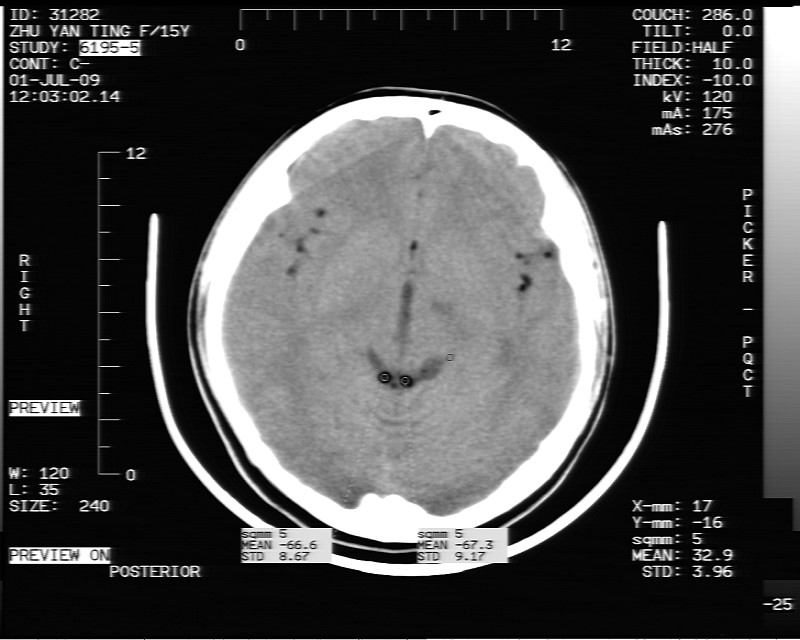

以下是引用余辉在2009-7-1 17:20:00的发言:[br]病变ct值-20至-80[br]考虑脑内脂肪瘤破裂,瘤主体应该在右侧桥小脑角池及鞍上池[br]鞍上池病灶面积较大,ct值应该能够测准,应此病灶应该就是脂肪密度,病灶密度有ct值-20至-80hu,为成熟脂肪密度,因此考虑脂肪瘤,也不除外其他含成熟脂肪的病灶[br]皮样囊肿密度应该稍高一点

以下是引用zjzjr在2009-7-1 16:52:00的发言:[br]支持皮样囊肿破裂.,表皮样囊肿一般密度均高.[br][br][本贴已被 zjzjr 于 2009-7-1 16:52:29 修改过]